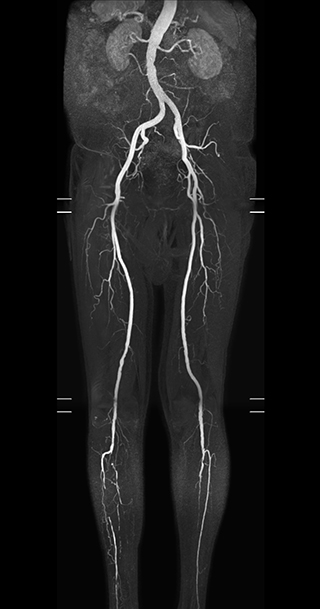

Subtractionless MRA run-off studies with exceptional spatial and temporal resolution

“In our peripheral MRA run-off studies with Ambition we realize key benefits, including outstanding image quality and significantly reduced breath-hold and scan times, which not only benefit the patient, but also provide the opportunity to add sequences that could aid in diagnosis,” Dr. Peña says.

“Before we had Ingenia Ambition, our CE-MRA run-off studies would first acquire a dynamic pre-contrast scan with 20-25-second breath-holds, then inject the contrast, do another acquisition and then subtract the two,” says Avila. “Now, mDIXON XD allows us to complete the study in just one single pass – without need for a pre-exam – which eliminates subtraction artifacts and almost halves the scan time. In addition, mDIXON provides much better background suppression, which really improves vesselto-background contrast. And, thanks to Compressed SENSE, the single breath-hold is not long and we improve image resolution.”

“Because mDIXON XD provides subtractionless fat-free imaging, we get much better background suppression, which really helps the vessels stand out”

MRA run-off study with mDIXON

The subtractionless peripheral MR angiography shows improved vessel-to-background contrast and high resolution. Ingenia Ambition 1.5T.

Station

Ingenia Ambition

Pelvis

Voxels 1.3 x 1.3 x 3.2 mm, FOV 430 mm, 125 slices

Upper legs

Lower legs

Voxels 1.0 x 0.82 x 2.0 mm, FOV 430 mm, 125 slices

Time saved enables addition of useful diagnostic sequences

The time saved by Compressed SENSE and mDIXON XD is sometimes used to include additional sequences. An example are peripheral MRA studies, in which Compressed SENSE and mDIXON XD help achieve a 5- to 10-minute reduction in scanning time. This brings the total time down, from the 45 minutes needed with their previous system to about 30 to 35 minutes on Ingenia Ambition, thus providing ample time to include additional sequences.

“These scans are so fast now that we have been able to add a non-contrast MRA sequence within the same timeslot. We compare the respective image quality with the goal to determine whether the non-contrast sequence could be an alternative for patients who can’t tolerate gadolinium contrast agents due to poor kidney function,” says Avila. “We find the image quality of the non-contrast sequence so good that we can now also offer peripheral MRA to these patients whom we had been unable to serve before Ambition, so that has been great.”